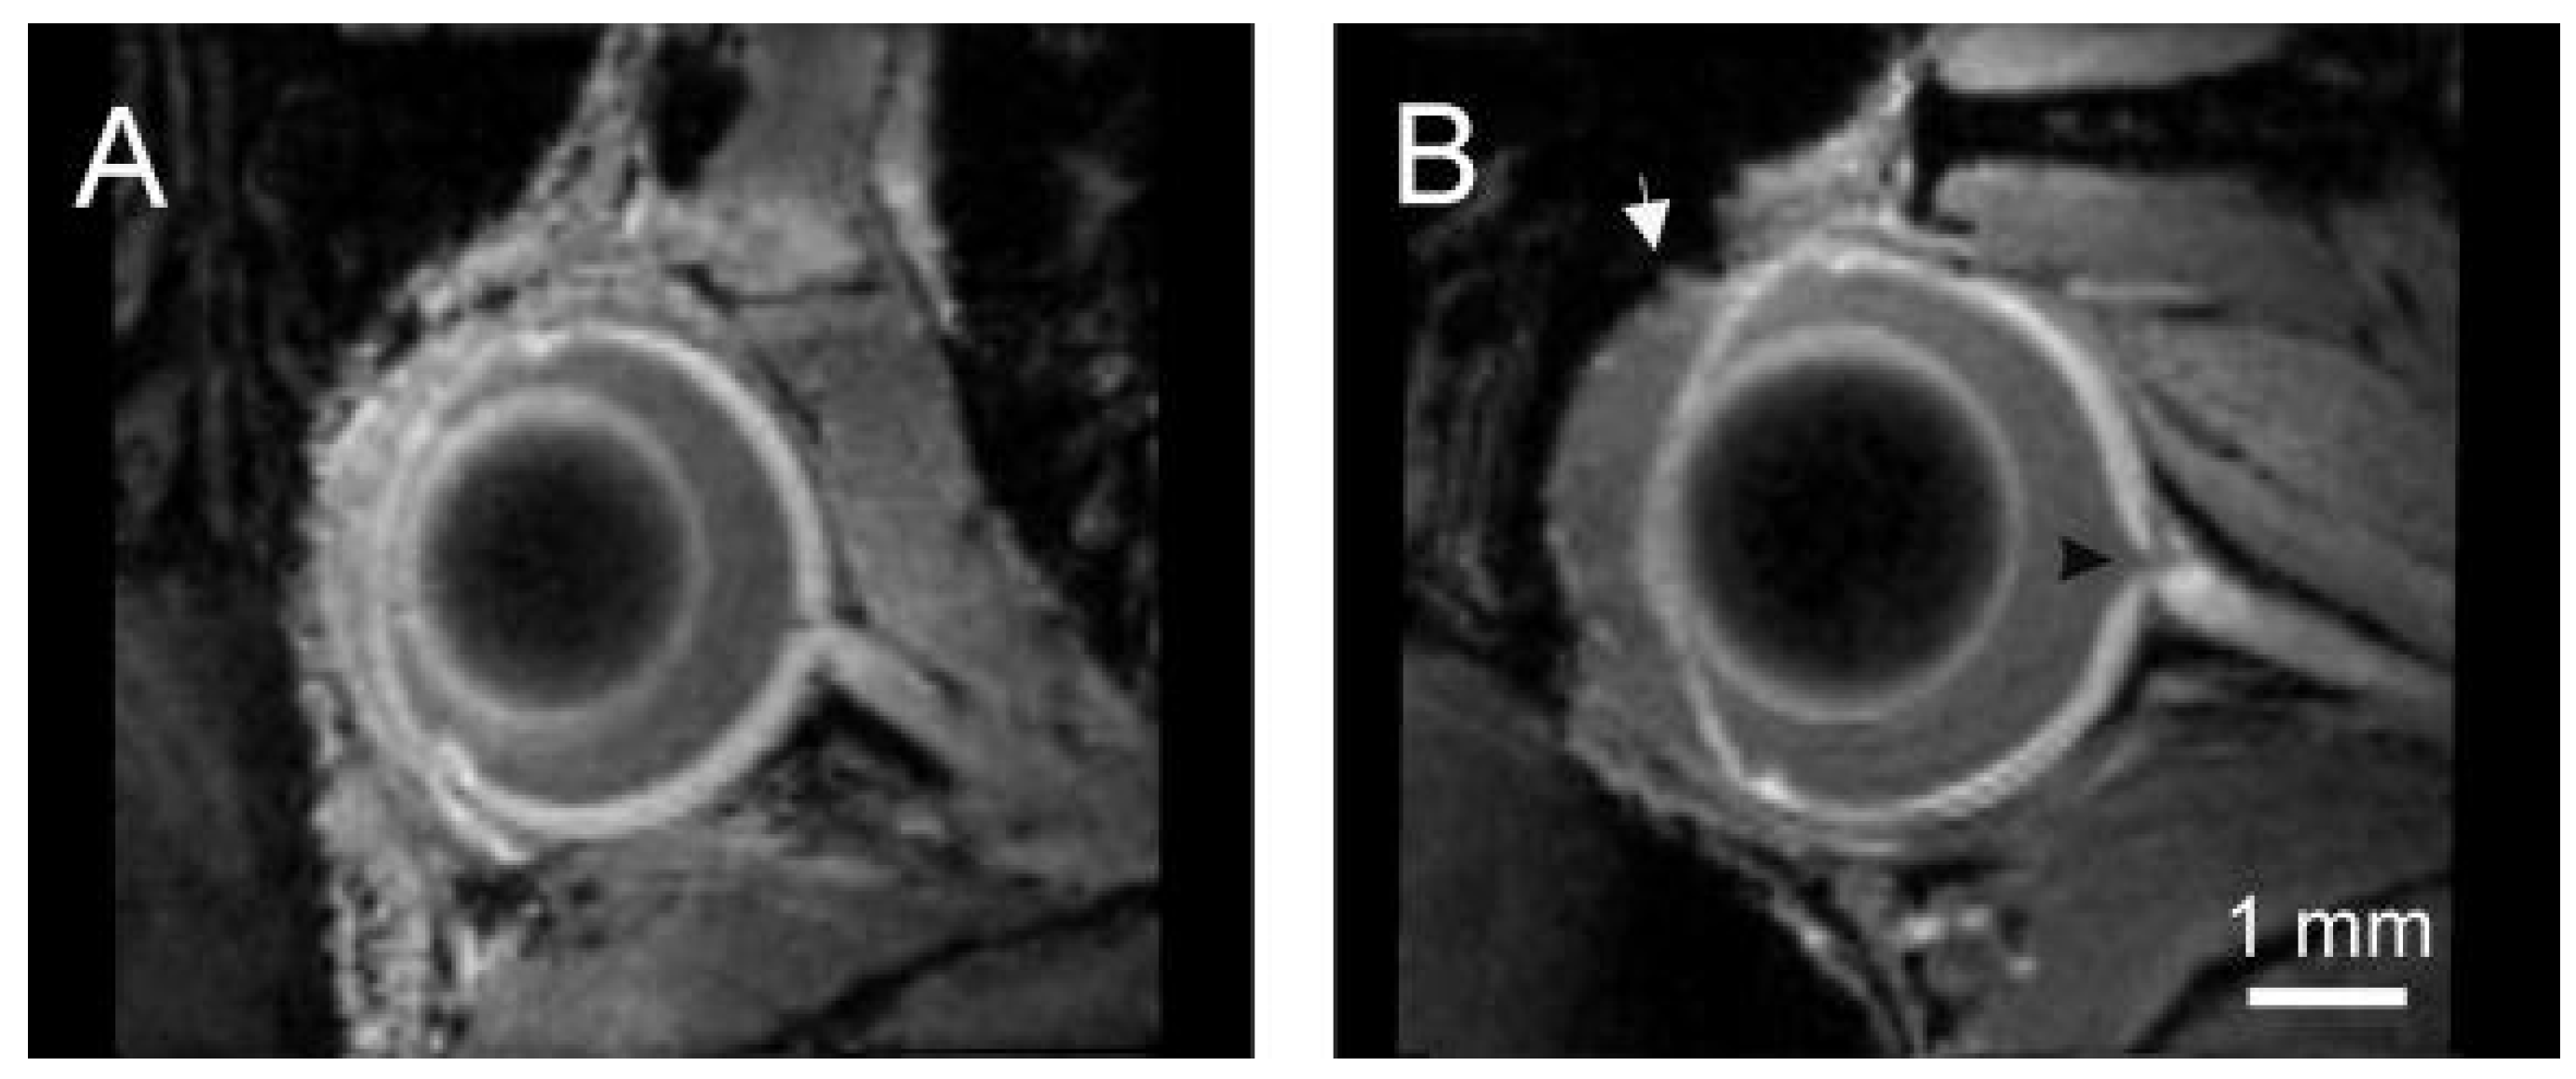

- Crosbie, D.E.; Keaney, J.; Tam, L.C.S.; Stamer, W.D.; Campbell, M.; Humphries, P. Age-related changes in eye morphology and aqueous humor dynamics in DBA/2J mice using contrast-enhanced ocular MRI. Magn. Reson. Imaging 2019, 59, 10–16. [Google Scholar] [CrossRef]

- Fiedorowicz, M.; Orzel, J.; Kossowski, B.; Welniak-Kaminska, M.; Choragiewicz, T.; Swiatkiewicz, M.; Rejdak, R.; Bogorodzki, P.; Grieb, P. Anterograde transport in axons of the retinal ganglion cells and its relationship to the intraocular pressure during aging in mice with hereditary pigmentary glaucoma. Curr. Eye Res. 2017, 43, 539–546. [Google Scholar] [CrossRef] [PubMed]

- Fiedorowicz, M.; Wełniak-Kamińska, M.; Świątkiewicz, M.; Orzeł, J.; Chorągiewicz, T.; Toro, M.D.; Rejdak, R.; Bogorodzki, P.; Grieb, P. Changes of ocular dimensions as a marker of disease progression in a murine model of pigmentary glaucoma. Front. Pharmacol. 2020, 11. [Google Scholar] [CrossRef]